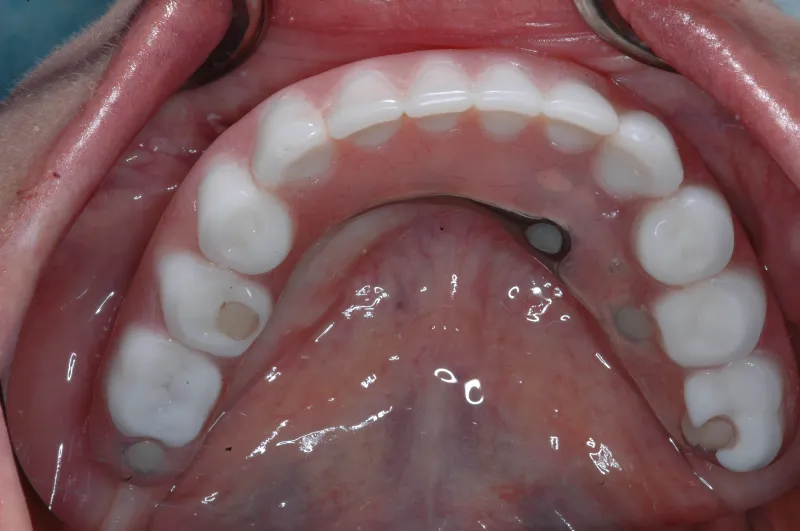

Implant dentures are designed to be fixed (screwed in place) or removable. The design is based on the number of implants present and the amount of bone loss that has already occurred. The fixed denture requires 4-6 implants . A removable implant supported denture can be made on as few as two implants. Sometimes the budget or insurance coverage will dictate which option you decide on. Most patients prefer the fixed type implant denture. These types of dentures eliminate the need for denture adhesive.